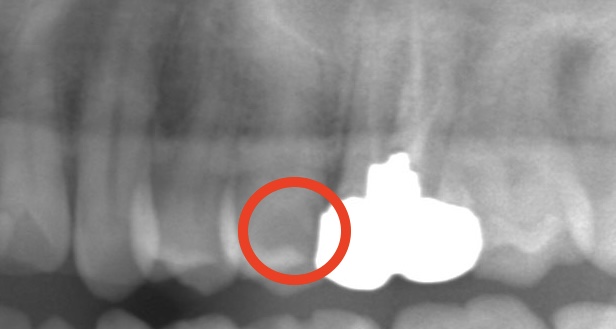

同じ患者さんの別日です。

先程の写真と比べるとどうでしょう。

赤い部分が減り白い部分が増えてきましたね!